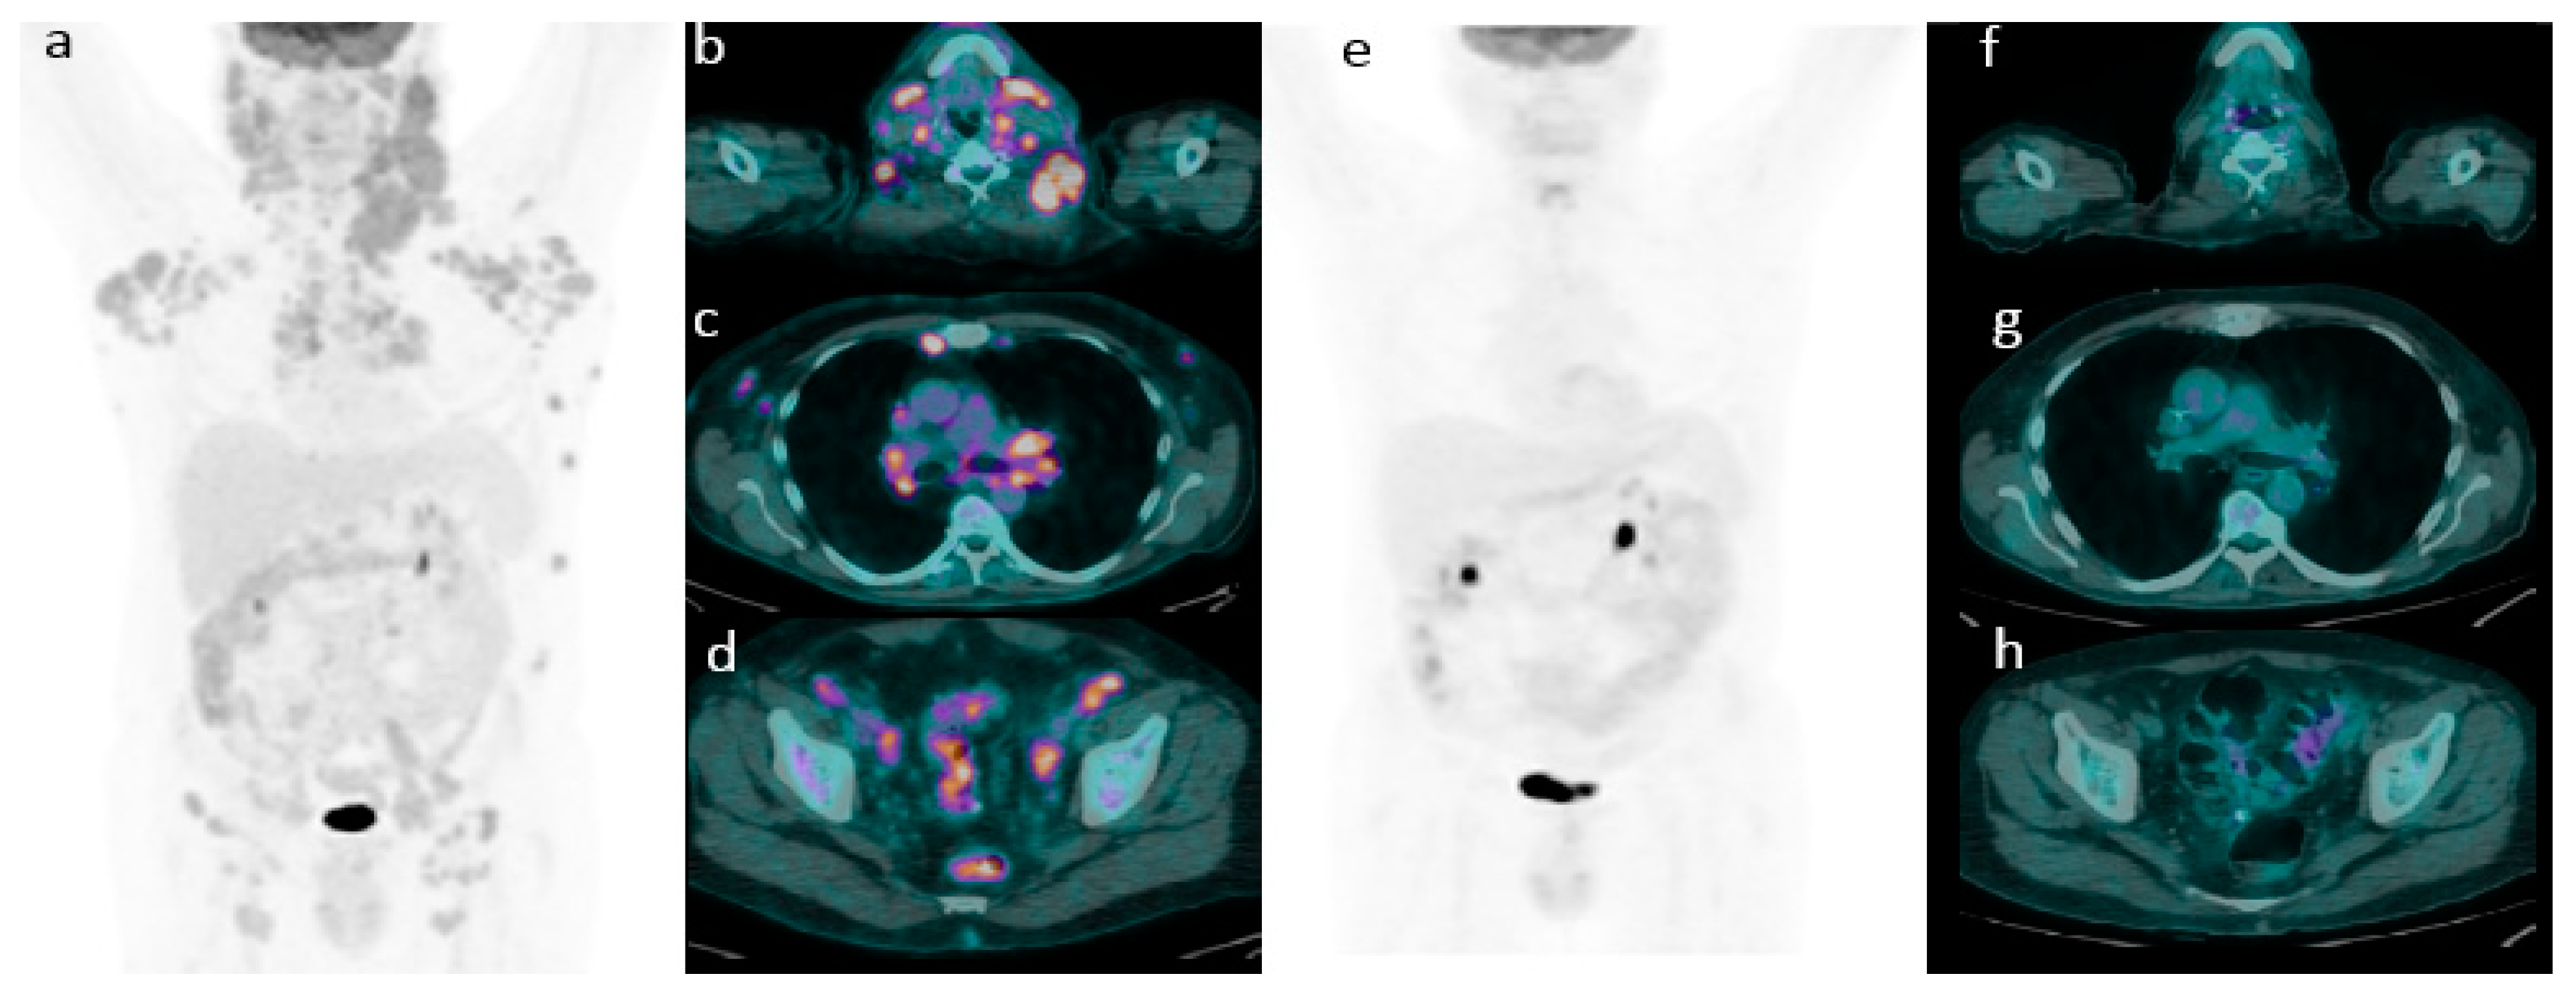

2.2. 18F-FDG PET/CT Evaluation for Initial Staging

Application of Deauville Criteria